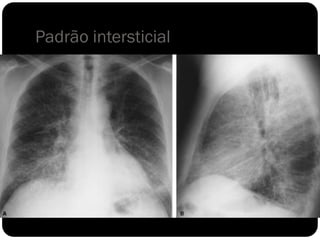

Padrão intersticial

 O interstício pulmonar é todo o tecido conjuntivo de

sustentação que mantém a arquitetura alveolar. Os vasos,

brônquios e linfáticos situam-se no interstício.

 Infiltrações intersticiais parenquimatosas podem aparecer na

forma de padrão

reticular

micronodular

reticulonodular.

 Sinônimo de espessamento septal: Linha de Kerley

Padrão intersticial - micronodular

 Pneumonia intersticial é tipicamente viral;

 Pneumonia alveolar é tipicamente bacteriana;